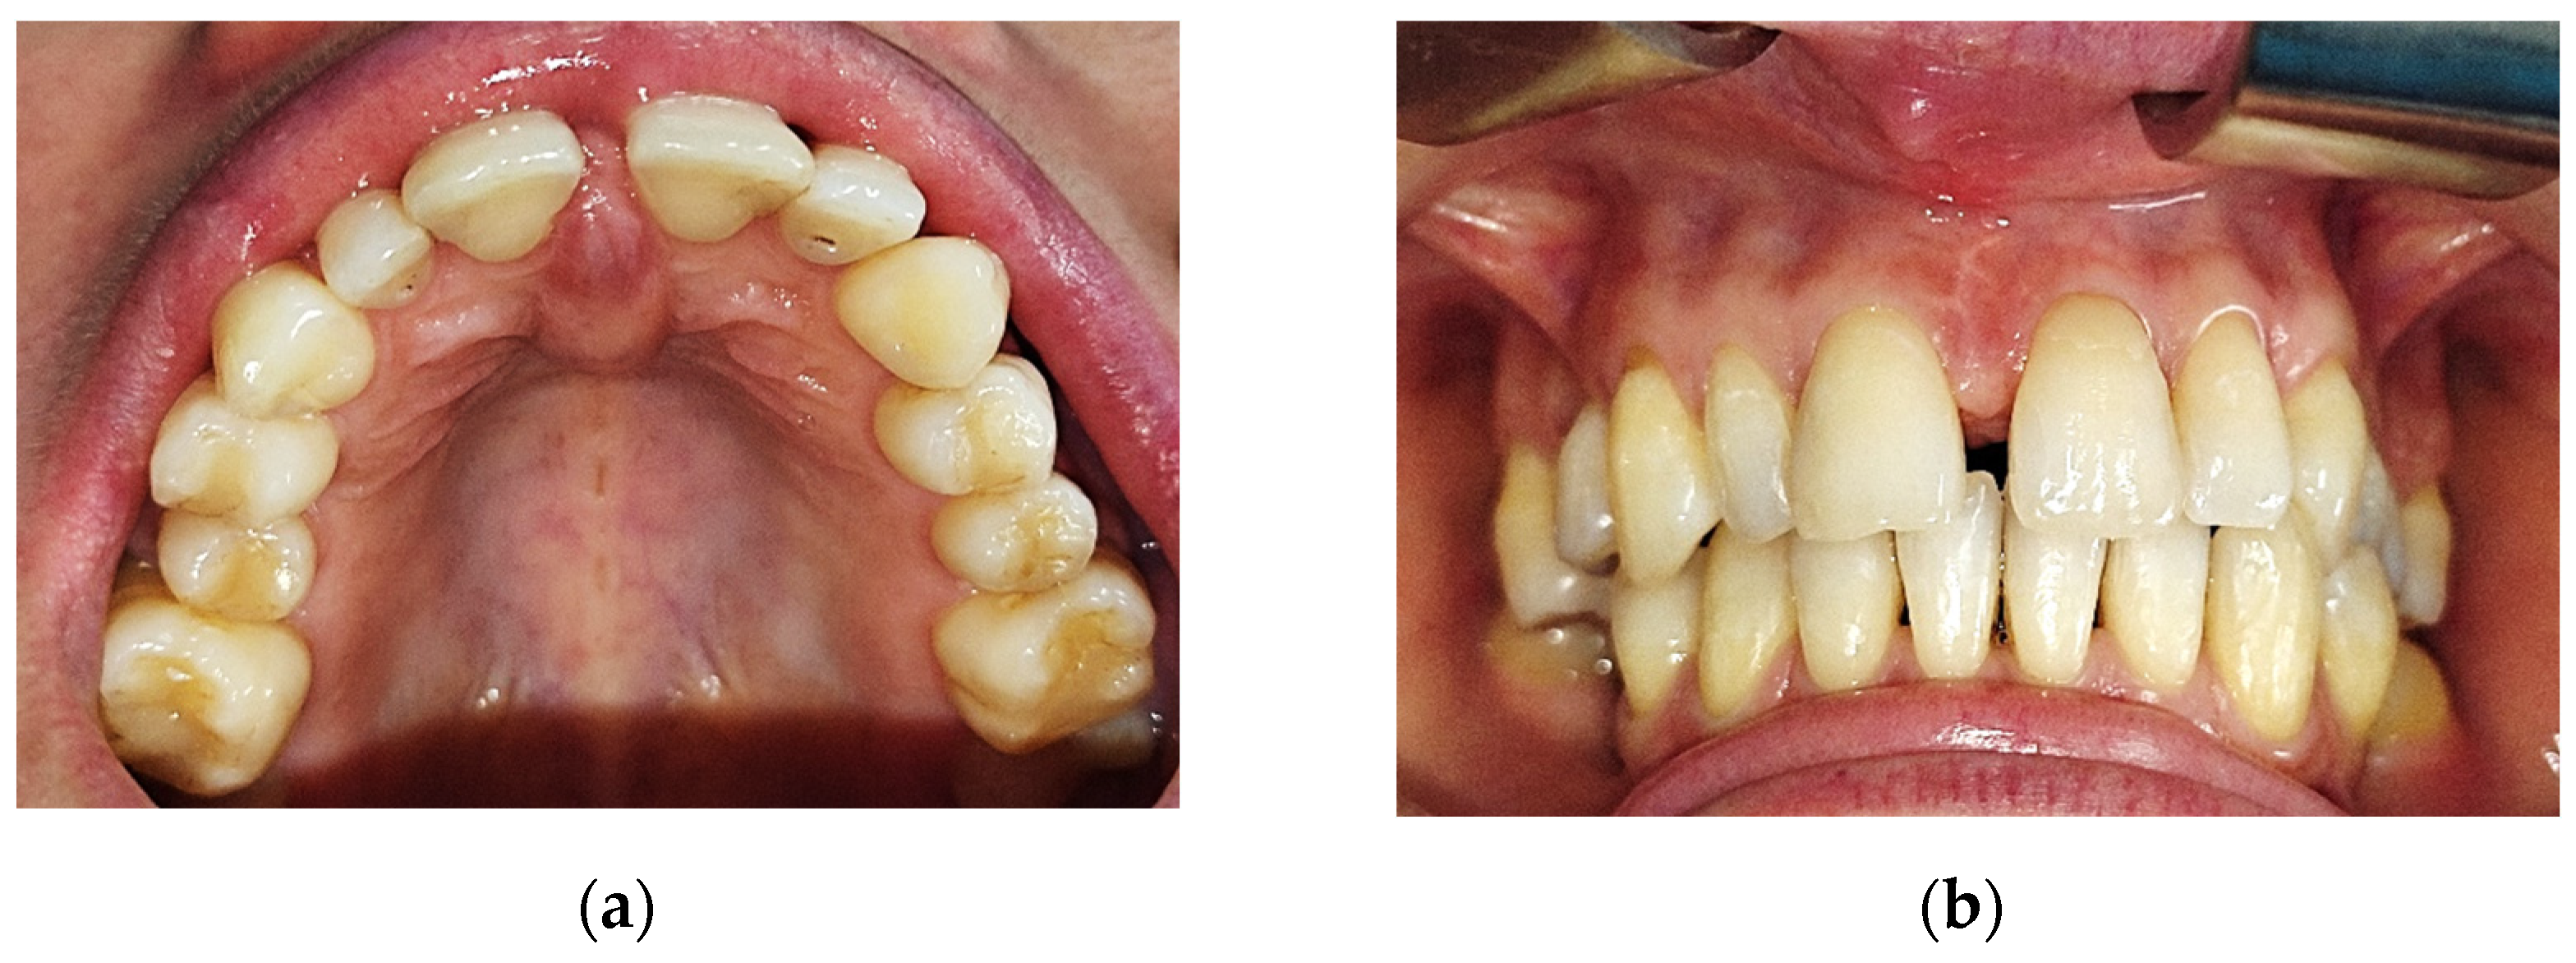

A cone beam computed tomography image (CBCT) did not reveal any changes of the subjacent bone structure in the anterior hard palate, suggesting the sole involvement of the soft tissue (Figure 2).

Figure 2. Cone beam computed tomography showed no underlying bone structure alteration.